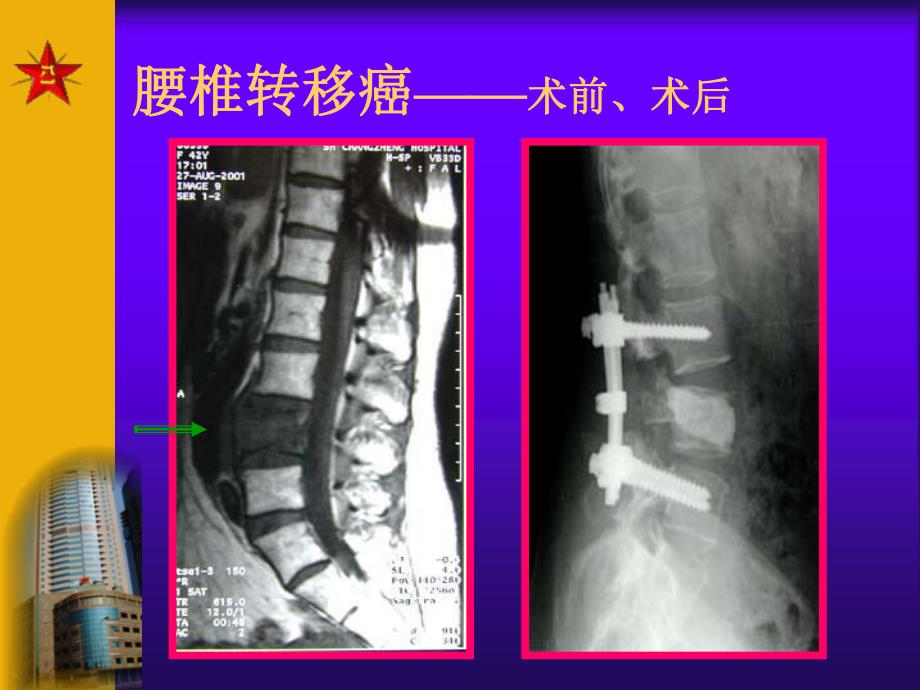

1、骨肿瘤骨肿瘤 Bone TumorBone Tumor第一节 概述发病率:1,098/10万挑战保肢手术 椎体:整体切除+固定术希望:攻克骨肿瘤重要性:四肢:致残率、死亡率高 脊柱:瘫痪腰椎转移癌腰椎转移癌术前、术后术前、术后神经鞘膜瘤病例保肢手术术 前术 后一、分 类原发性起源于骨的基本组织:骨、软骨、纤维、间质、组织细胞 起源于骨的附属组织:脉管、神经、脂肪、骨髓、滑膜等继发性转移性骨肿瘤:乳腺、肺癌、前列腺瘤样病损骨囊肿、动脉瘤样骨囊肿、骨纤维结构不良、嗜酸性肉芽肿等 二、各种肿瘤发生率一、不同的肿瘤类型良性骨肿瘤:骨软骨瘤、软骨瘤、骨瘤、骨性纤维瘤恶性骨肿瘤:骨巨细胞瘤、骨肉瘤、软骨肉